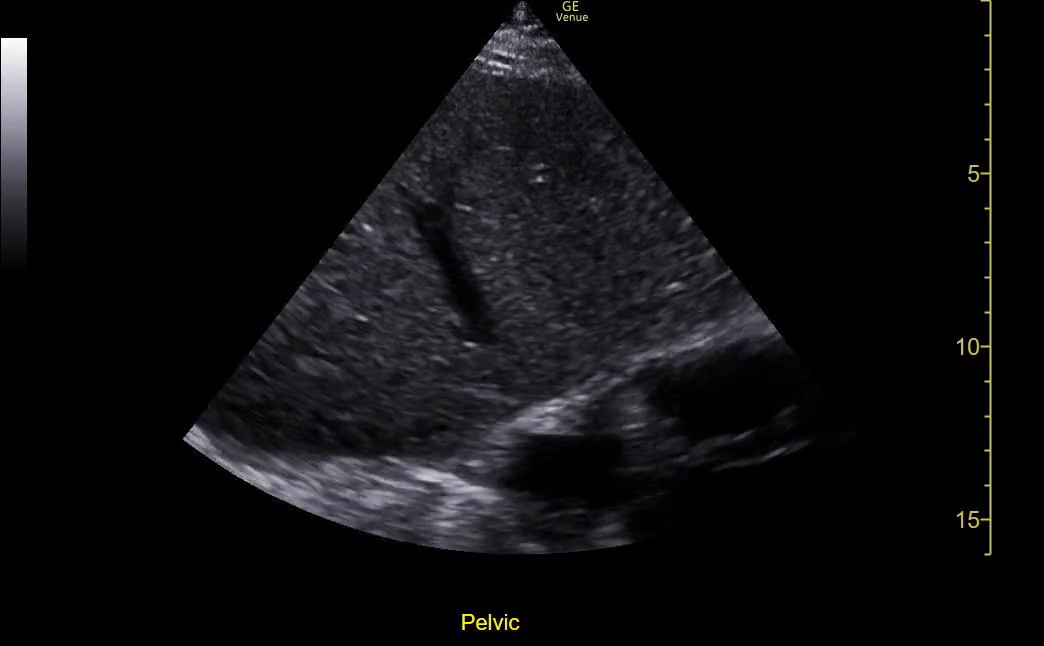

Too little depth

In general, we want to see the entire AOI on the screen – none of it should be cut off. The concern in this case is not wasted pixels on the screen but incomplete visualization of the AOI.